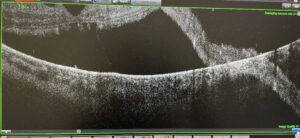

That was all under control, but she asked if she could “borrow his eyeballs. I wanted to be sure that all of my data was transferring from my autorefractor to the electronic health records,” she recalls. He agreed, noting that his vision in his left eye had been a little dark and wavy. “Luckily, I had my brand new Maestro OCT, an ocular coherence tomographer, already set up next to the autorefractor and I decided to scan James just in case. When I scanned the right eye, and I saw a large retinal detachment with macula on, and in the left eye, the retina was fully detached with macula off.”

Dr. Monks immediately began to quiz him on whether he recently had surgery or a change in medications. She sent the images to a retina specialist, who quickly contacted another. “She would not let me leave until I had an appointment scheduled,” Keyser says. A day later, he had a three-hour visit with the specialist who was able to laser the partial detachment. On Sept. 12—just 48 hours after he first walked into Dr. Monks’ office—Keyser had his procedure for the second eye.